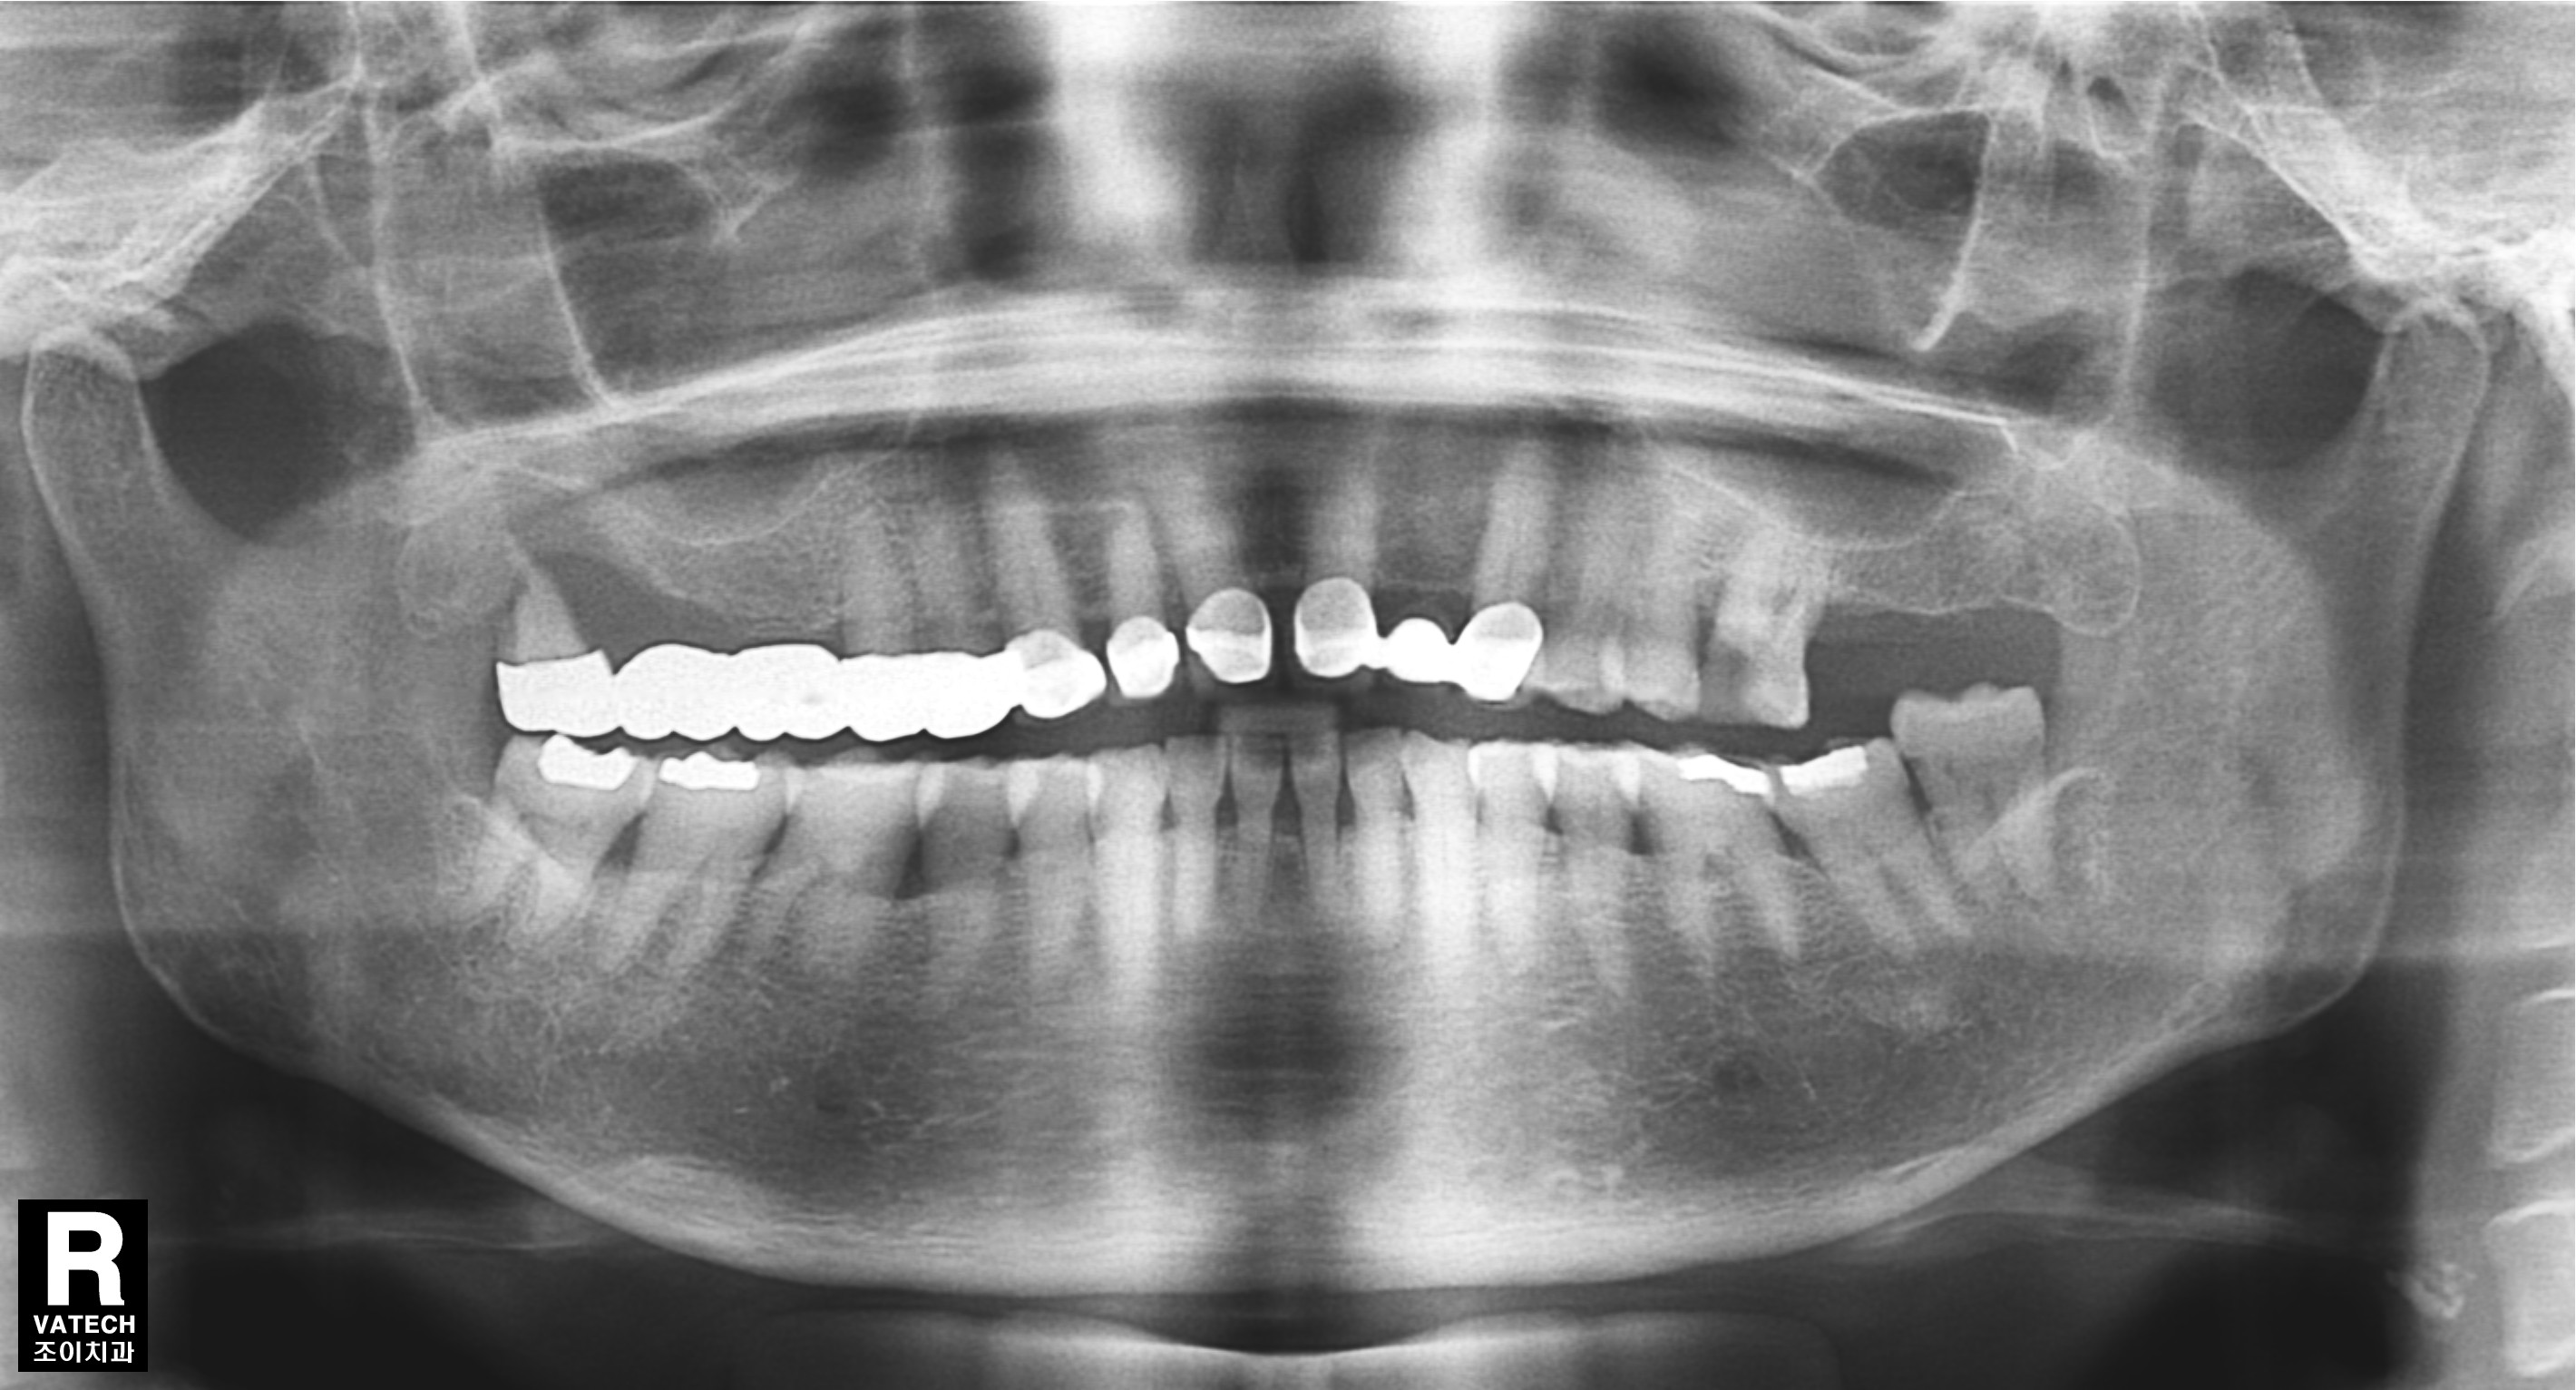

[임플란트] 제목 : 상악구치

흔히 일어나는 구치 상실의 수복 례